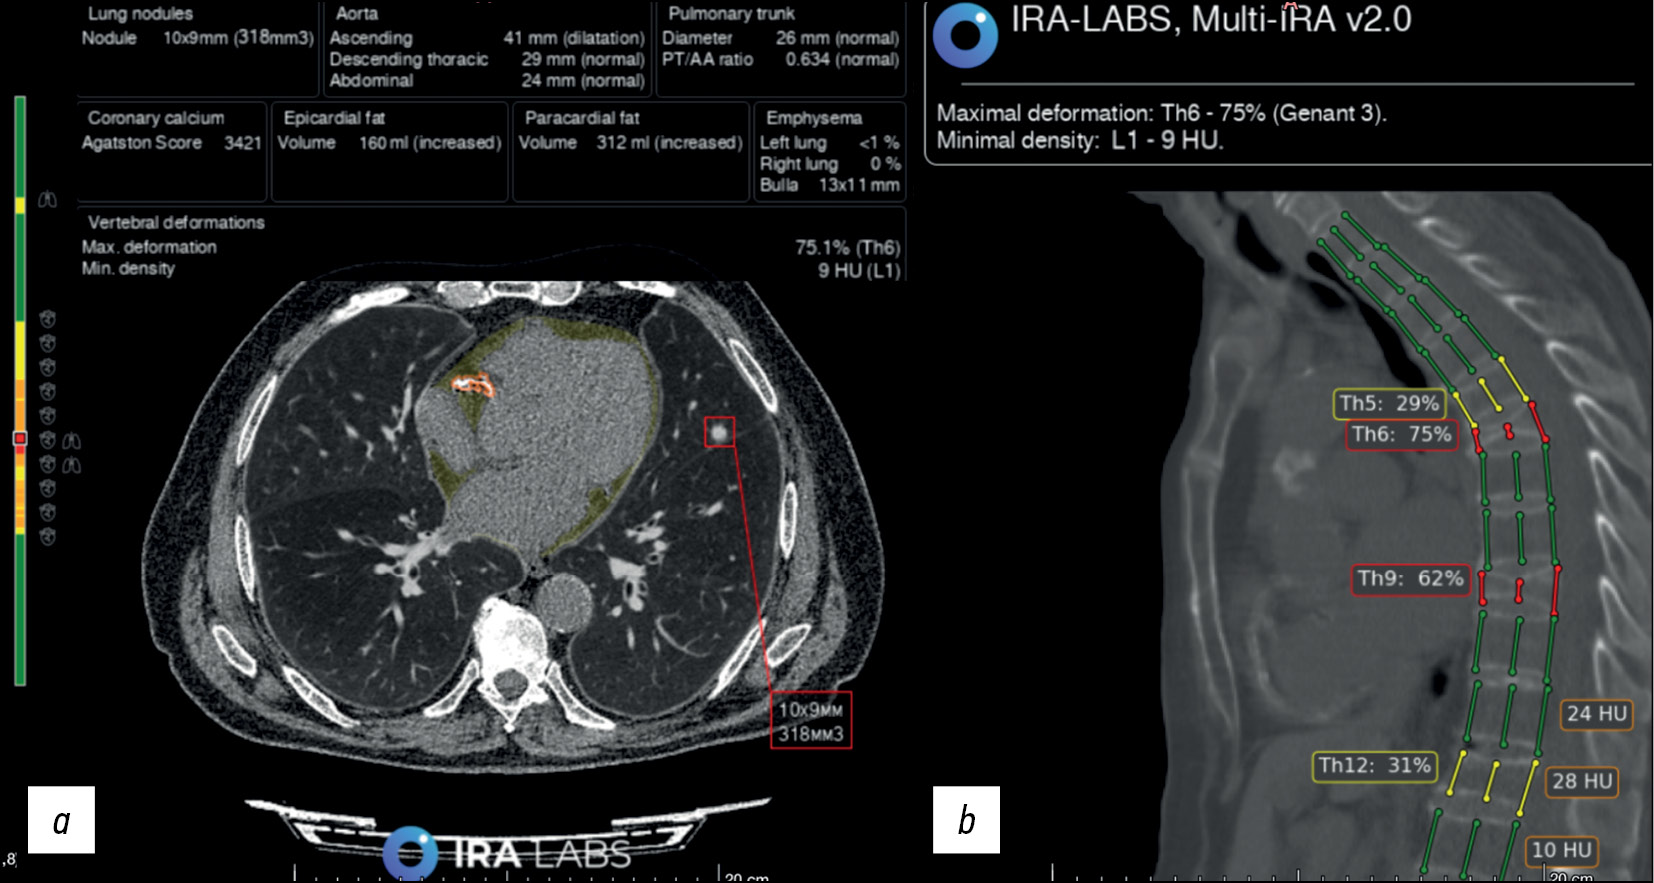

Fig. 7. An example of AI use. Patient B., 79 years old. Chest CT scans: a) axial section: a radiologist and an algorithm correctly identified a lung nodule in the left lung (indicated by a red square) and coronary calcification (outlined by an orange line). In addition, the algorithm indicated an increase in the volume of epicardial fat (filled in yellow; this pathological finding was not considered in the study); b) sagittal section: a radiologist and an algorithm correctly identified compression fractures of Th6 and Th9 vertebral bodies, Genant 3 (three columns are marked with red lines); however, the radiologist did not indicate deformities of Th5 and Th12 vertebral bodies, Genant 2 (three columns are marked with yellow lines) in the protocol.